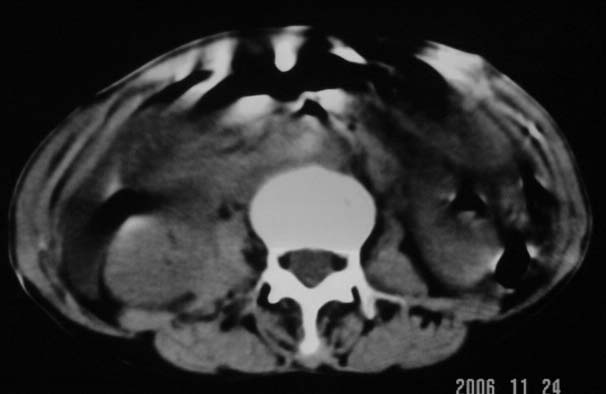

仰卧位见:肝前间隙及肝脾间隙内可见新月形气体密度影,边缘清楚,侧卧位见气体随体位改变而移动,ct值约-929hu。膈下、肝下间隙及部分肠间隙可见液性密度影。考虑:1、上腹部空腔脏器穿孔,以胃穿孔可能性大。2、少量腹水。

仰卧位见:肝前间隙及肝脾间隙内可见新月形气体密度影,边缘清楚,侧卧位见气体随体位改变而移动,ct值约-929hu。膈下、肝下间隙及部分肠间隙可见液性密度影。考虑:1、上腹部空腔脏器穿孔,结合临床,首先考虑胃穿孔可能性大。2、少量腹水

补充--肝门及肝肾间隙以见积气显示。

支持消化道空腔脏器穿孔(腹腔内大量游离气体影,小网膜囊内亦见气体影),少量腹水。